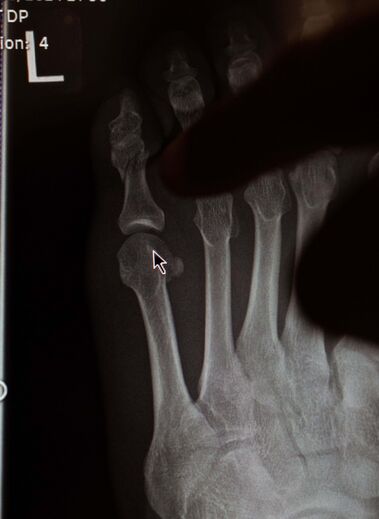

Depois de ter anunciado a desistência da luta no UFC 303 por conta de uma lesão, Conor McGregor foi alvo de duras críticas, com acusações de que estaria a fugir do combate com Michael Chandler e, por isso, inventou uma lesão. Farto de todos esses ataques, o irlandês de 35 anos utilizou as redes sociais para mostrar o estado em que ficou o seu pé (o motivo da desistência) e para deixar a garantia de que voltará... até porque um novo Bugatti para comprar.

"Meu, estávamos tão prontos para esta luta, que é mesmo doloroso isto. Quero aquele novo Bugatti. Como é que vou justificar a mim mesmo esse investimento sem receber destas lutas? Tivemos um momento de desconcentração e entrámos na sessão de treino sem utilizar o equipamento de proteção completo. E acabei por bater com o dedo e parti-o. Agora preciso de umas semanas. A próxima vez que me virem a entrar no octógono será a 100%. Os meus fãs merecem e estamos perto disso. Uma pequena desconcentração e veio uma lesão. Agora é aprender com a lição e seguir em frente. Vou voltar. Tenho de. Tenho mais duas lutas neste contrato. Tenho Bugattis e mais iates em mente. Vim aqui para brilhar, só preciso do meu tempo. Porque ainda tenho iates, Bentleys, mansões e tudo o resto. Vocês conhecem-me. Vemo-nos em breve. Seja o Chandler ou não", escreveu o irlandês, no Instagram.